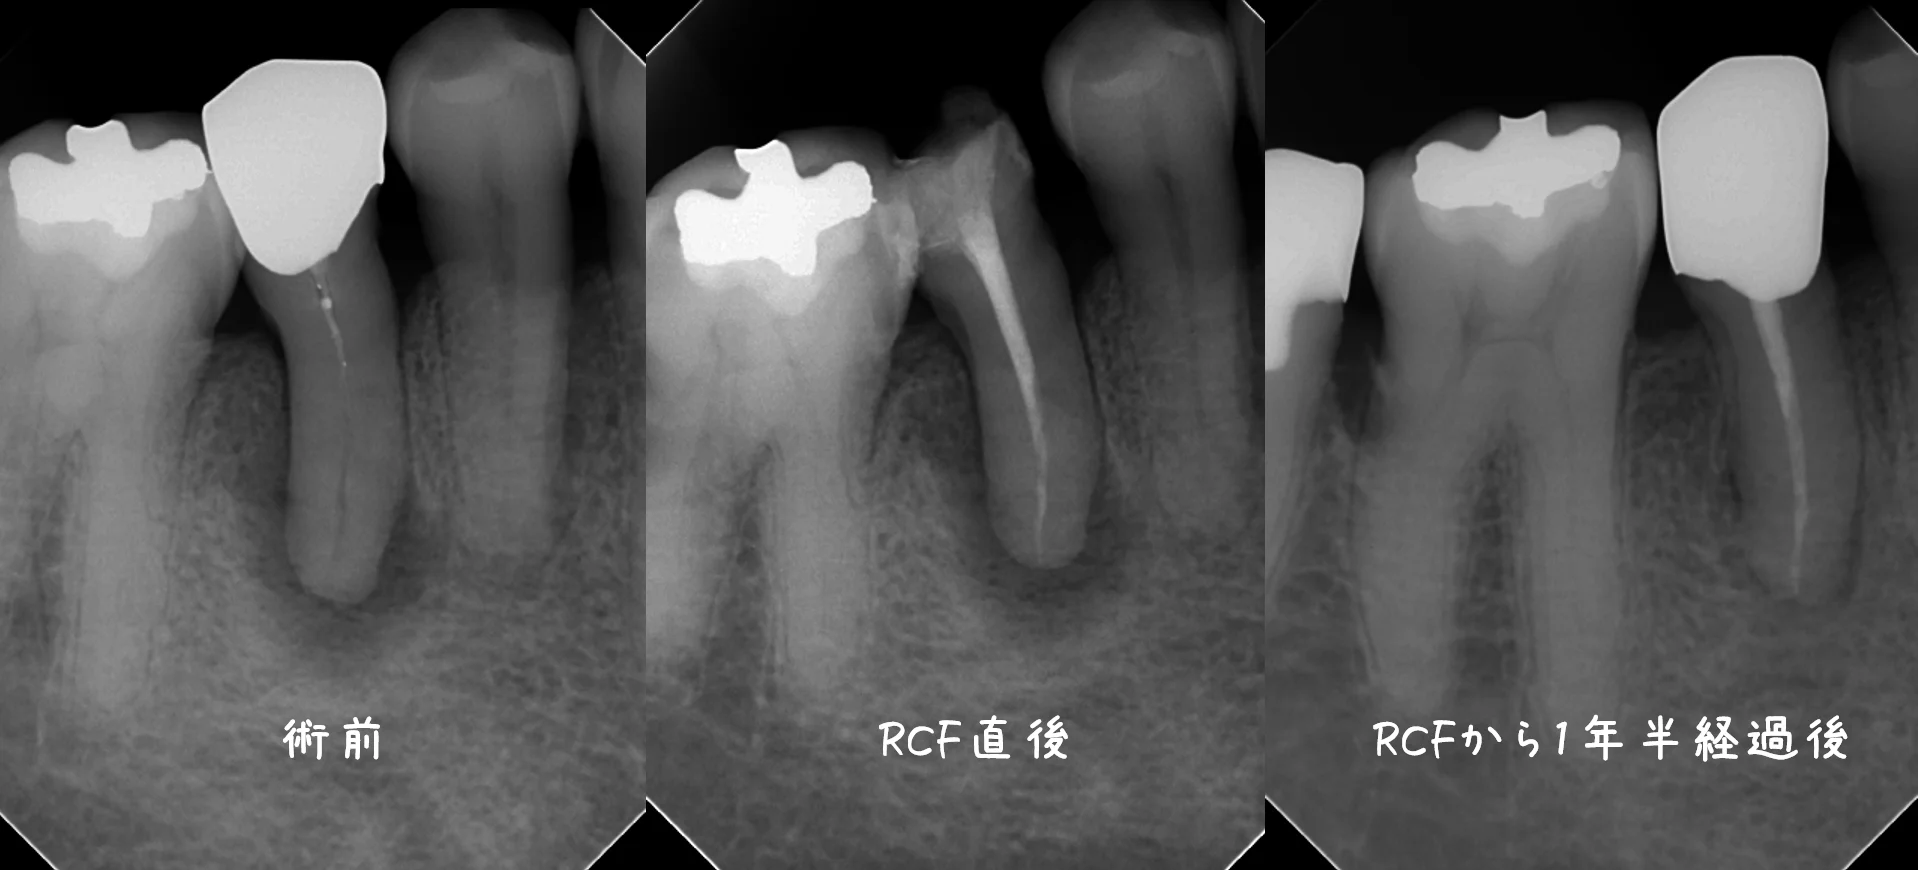

処置開始~神経の治療完了時(RCF時)~1年半経過後を並べるとこうなります。

こうみると随分と良くなっているのが分かるかと思います。

それでもうっすら根の先の骨には空洞が残っていますね。

違和感や食事時の痛みなどは出ていませんので、特に問題はありませんが・・・

骨が完全に治るのには恐らくあと1年ほどは掛かりそうですね・・・。